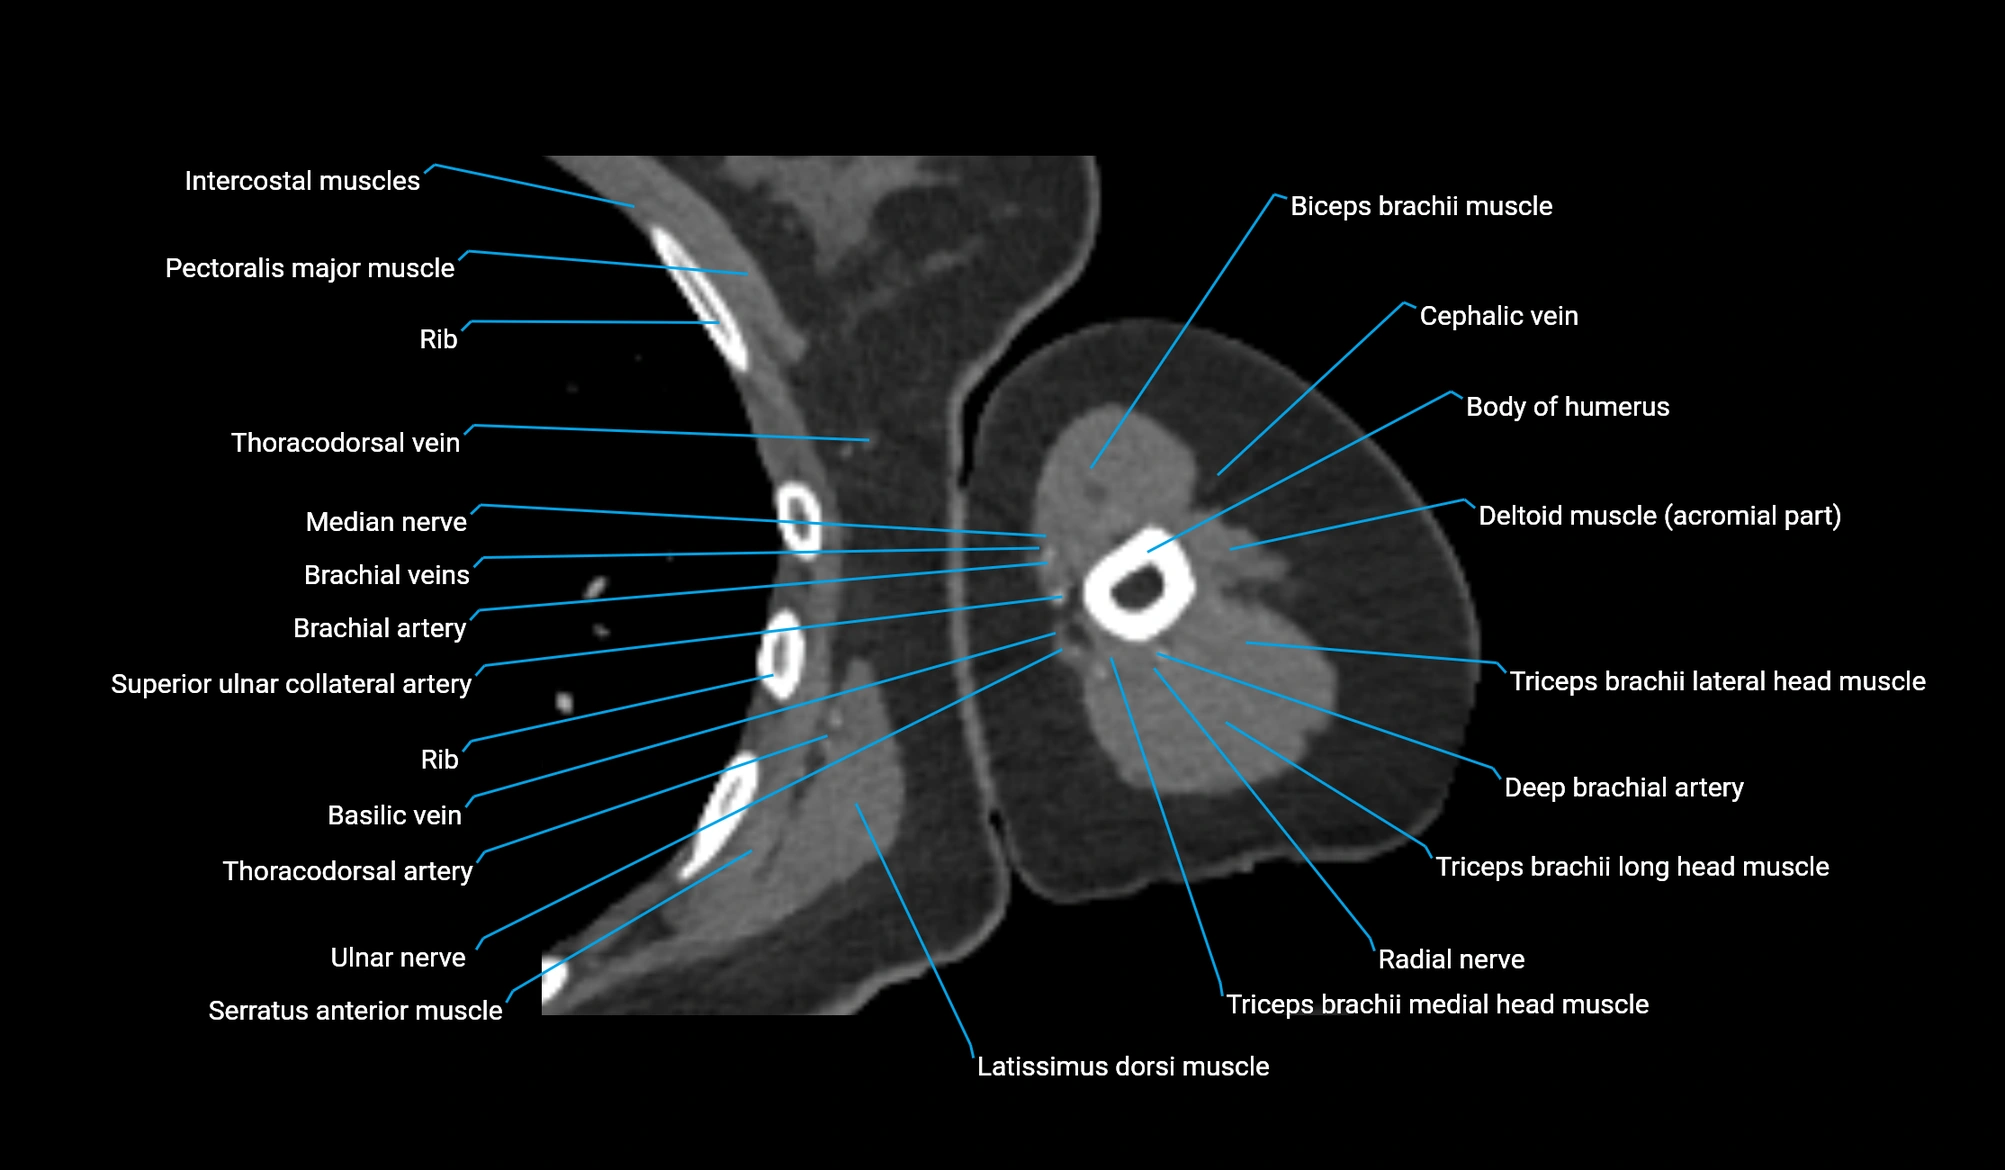

CT image